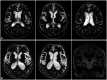

Parkinsonism is a clinical syndrome presenting with bradykinesia, tremor, rigidity, and postural instability. Nonmotor symptoms have recently been included in the parkinsonian syndrome, which was traditionally associated with motor symptoms only. Various pathologically distinct and unrelated diseases have the same clinical manifestations as parkinsonism or parkinsonian syndrome. The etiologies of parkinsonism are classified as neurodegenerative diseases related to the accumulation of toxic protein molecules or diseases that are not neurodegenerative. The former class includes Parkinson's disease (PD), multiple-system atrophy, progressive supranuclear palsy, and corticobasal degeneration. Over the past decade, clinical diagnostic criteria have been validated and updated to improve the accuracy of diagnosing these diseases. The latter class of disorders unrelated to neurodegenerative diseases are classified as secondary parkinsonism, and include drug-induced parkinsonism (DIP), vascular parkinsonism, and idiopathic normal-pressure hydrocephalus (iNPH). DIP and iNPH are regarded as reversible and treatable forms of parkinsonism. However, studies have suggested that the absence of protein accumulation in the nervous system as well as managing the underlying causes do not guarantee recovery. Here we review the differential diagnosis of PD and parkinsonism, mainly focusing on the clinical aspects. In addition, we describe recent updates to the clinical criteria of various disorders sharing clinical symptoms with parkinsonism.